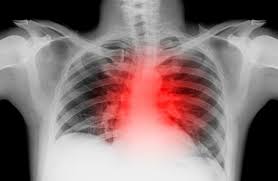

5. 오른쪽 가슴 통증과 호흡기 질환

호흡기 질환도 오른쪽 가슴 통증의 원인 중 하나입니다. 기침이나 호흡 곤란이 동반되는 경우, 폐렴이나 기흉과 같은 문제가 있을 수 있습니다. 이러한 증상이 나타나면 흉부 X-ray나 폐 CT 검사를 통해 호흡기 상태를 점검해야 합니다. 호흡기 문제가 확인된다면 적절한 치료를 통해 오른쪽 가슴 통증을 완화할 수 있습니다.